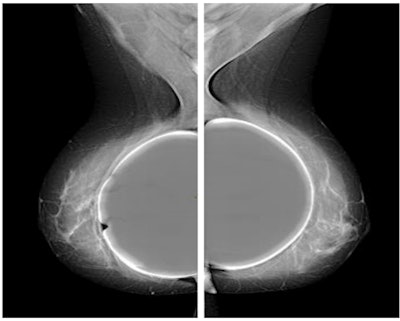

The women were divided into two groups. The first group included 15 women undergoing standard protocol with standard configuration for the automatic exposure control (AEC) algorithm present on the mammography unit, including eight projections: four with digital mammography that included the breast implant and four with tomosynthesis (with synthetic image) using the Eklund maneuver, a modified compression technique that can be used for patients with augmented or reconstructed breasts postmastectomy.

"In our patient cohort, we demonstrated that with the study in mammography mode and only four projections with prosthesis included, and using a standard exposure meter, the exam is associated with an average glandular dose of 7.5 mGy," the authors stated.

If the Eklund maneuver is also performed in tomosynthesis mode, the woman is exposed to an average of 11 mGy in total. A low-dose configuration of the AEC is associated instead with an average glandular dose equal to 9.2 mGy total. This configuration allowed a maximum amount of radiographic information currently possible, lowering the dose by 15%, while maintaining adequate image quality, they pointed out.